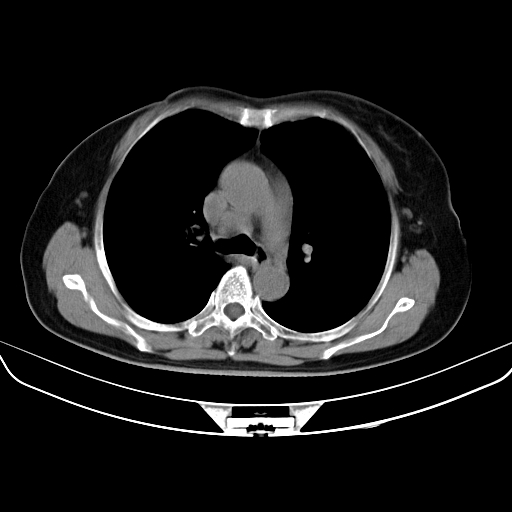

以下是引用zjzjr在2007-3-23 13:28:00的发言:[br]右肺上叶后段可见一结节状高密度影,可见毛刺征,胸膜凹陷征及血管导入征,纵隔内可见肿大淋巴结影.考虑右肺上叶周围型肺癌伴纵隔淋巴结转移.

以下是引用zjzjr在2007-3-23 13:28:00的发言:[br]右肺上叶后段可见一结节状高密度影,可见毛刺征,胸膜凹陷征及血管导入征,气管前腔静脉后可见肿大淋巴结影.考虑右肺上叶周围型肺癌伴纵隔淋巴结转移.